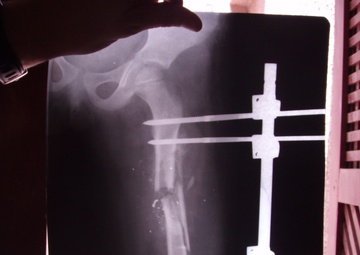

An X-ray of the shattered femur of a four-year-old Iraqi girl living in the Suleikh neighborhood of Adhamiyah who was hit by a stray bullet. Soldiers from the Fort Stewart, Ga.,-based A Troop, 3rd Squadron, 7th Cavalry Regiment, have made it their mission to make sure she gets proper medical attention....